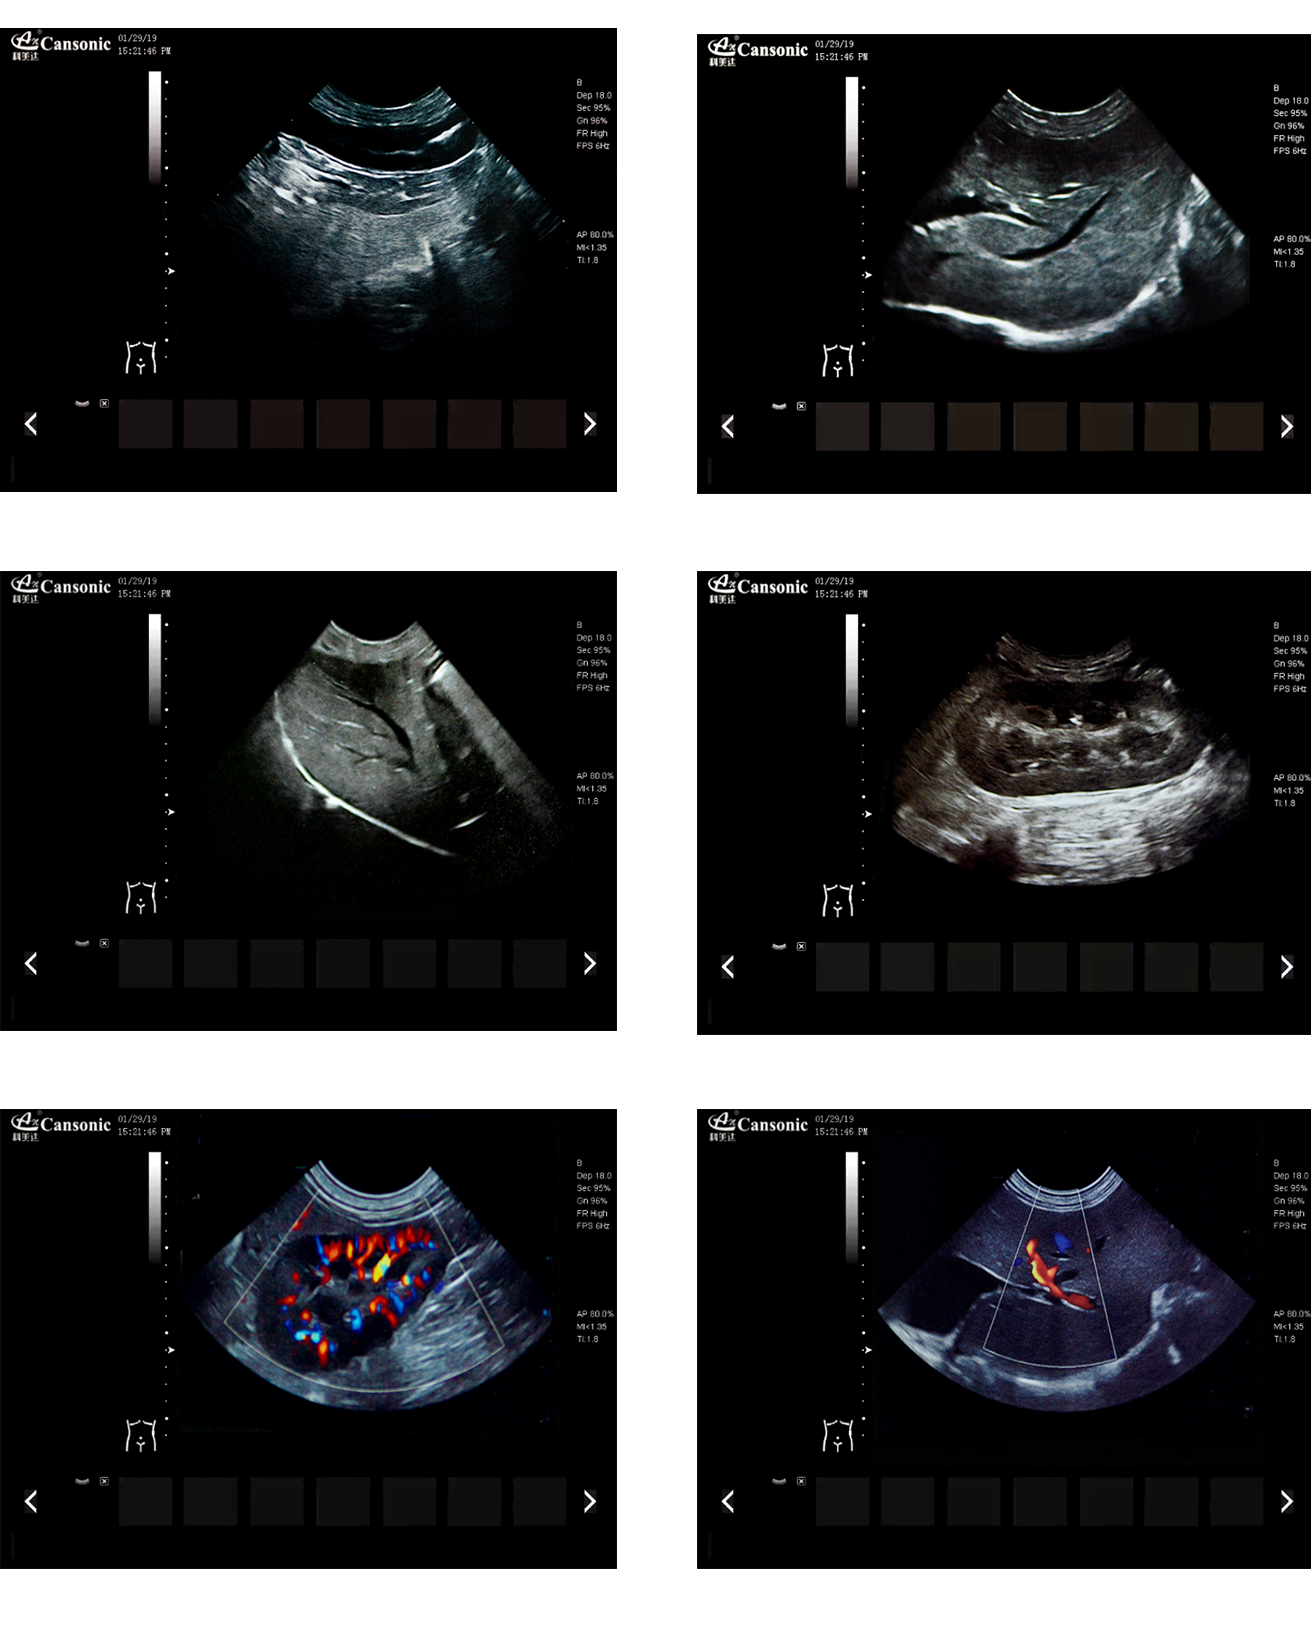

临床图示